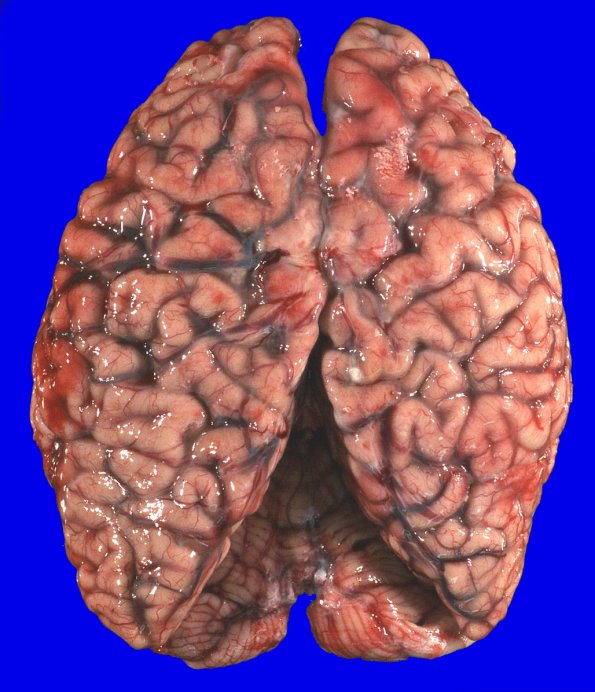

Washington University Experience | NEURODEGENERATION | Huntington Disease | 18A1 (Case 18) Gross _2

At autopsy the weight of the unfixed brain was 1110g. The sulcal-gyral pattern is normal, but the cortex shows mild diffuse atrophy. Coronal sections of the left cerebral hemisphere confirm diffuse mild cortical atrophy with relatively unremarkable subcortical white matter.